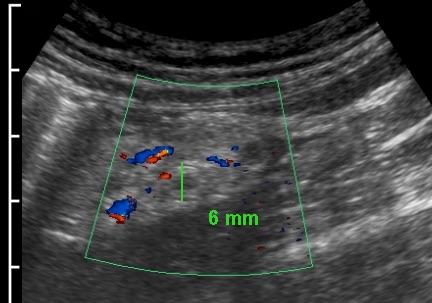

Ở người phụ nữ mang thai 11 tuần này, siêu âm xác nhận thai trong tử cung còn nguyên vẹn đồng thời phát hiện viêm ruột thừa cấp.

Lưu ý sự khác biệt về thang đo cm.

Phẫu thuật nội soi cắt bỏ ruột thừa viêm đã được thực hiện thành công.